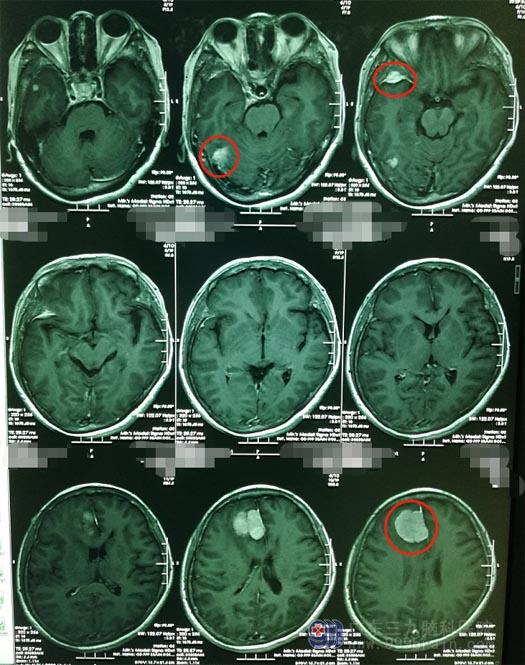

十多天前,高阿姨除了头痛,还出现了恶心呕吐,赶紧在当地医院做了头颅MRI检查,提示:右侧额部大脑镰旁、右侧颞下回旁、右侧小脑幕区多发脑膜瘤。听从了一位老乡的介绍,高阿姨来到广东三九脑科医院神经外五科,诊断“颅内多发占位”。

完善术前准备后,鲁明带领神经外五科治疗团队在全麻下行“右侧额部大脑镰旁、颞部多发脑膜瘤切除术”肿瘤位于大脑镰旁,大脑镰旁脑膜瘤起始于大脑镰,常埋入脑实质内并可向大脑镰两侧生长,肿瘤大多埋藏在大脑半球纵裂中,位置较深,所以暴露肿瘤位置成术中的难点;从周边逐步分离肿瘤,显微镜下予以分块全切除。手术顺利,重要神经及血管均没有损伤。